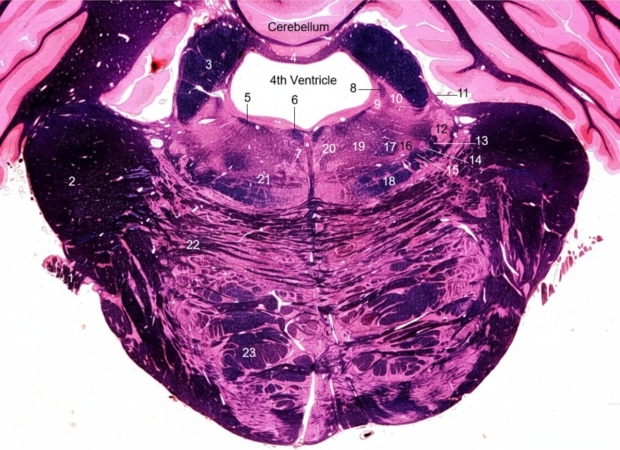

1. Trigeminal nerve

2. Middle cerebellar peduncle

3. Superior cerebellar peduncle

4. Superior medullary velum

5. Genus of facial nerve

6. Medial longitudinal fasciculus

7. Tectospinal tract

8. Mesencephalic tract and nucleus of trigeminal nerve

9. Locus ceruleus

10. Motor nucleus of trigeminal nerve

11. Ventral spinocerebellar tract

12. Sensory nucleus of trigeminal nerve